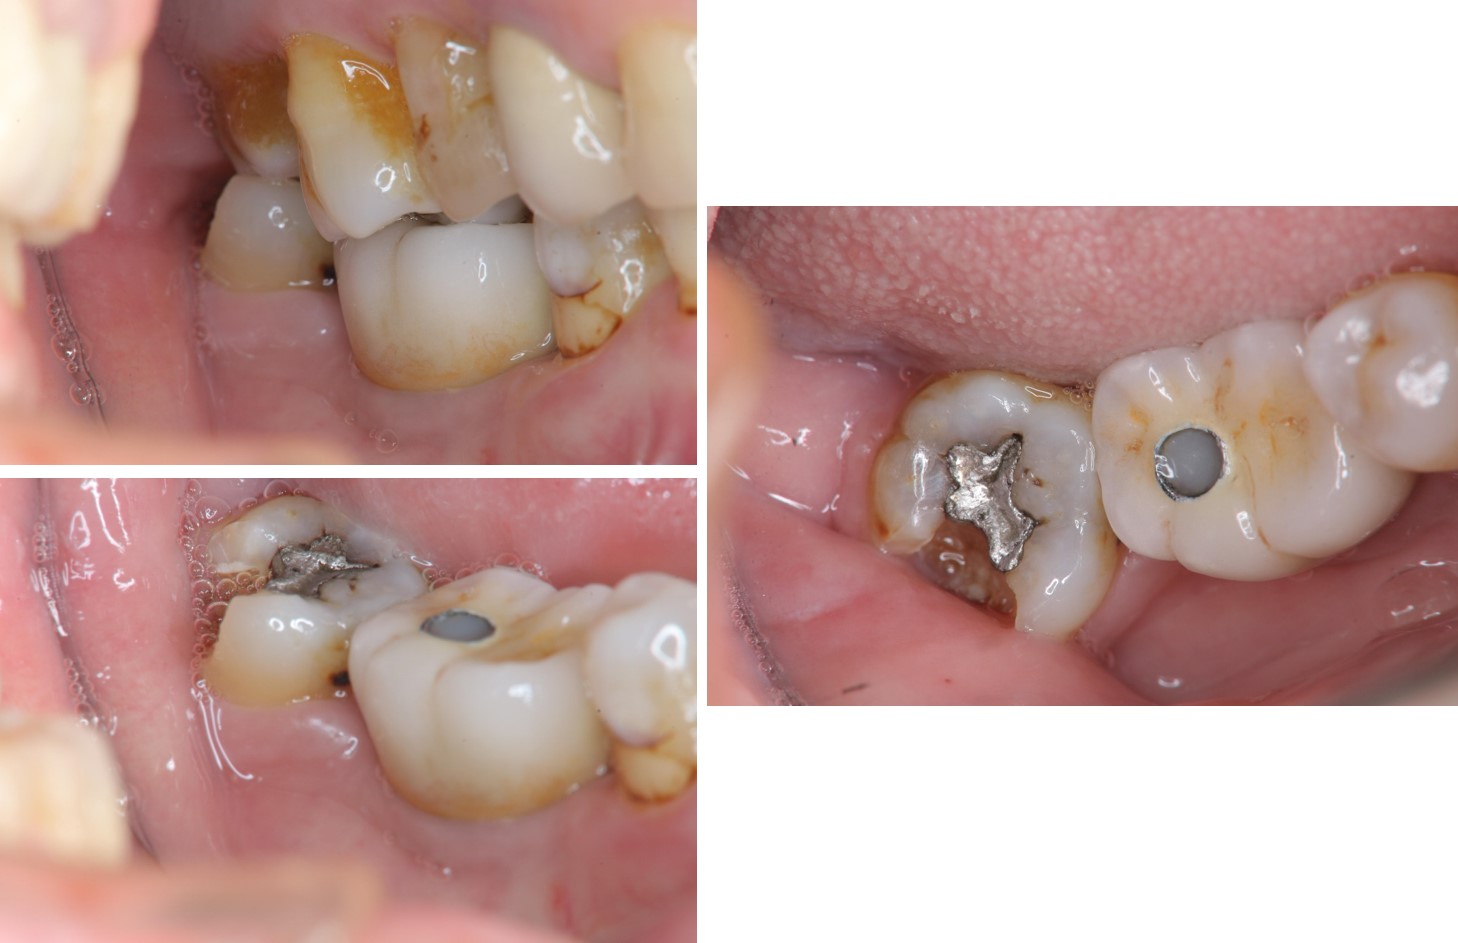

治療前,右下第三大臼齒冷熱敏感

治療前,蛀牙已侵犯至牙髓

顯微根管治療

鑄造金屬釘柱

水雷射牙冠增長手術

膺復前評估牙齦、牙齒狀態